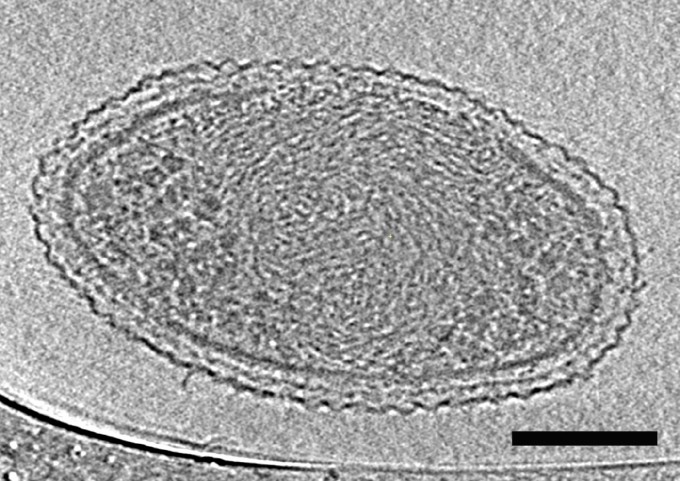

‘Heart on a chip’ reduces time and cost in drug testing for safety and efficacy

Replaces animal models, which have a high failure rate in predicting human reactions to new drugs